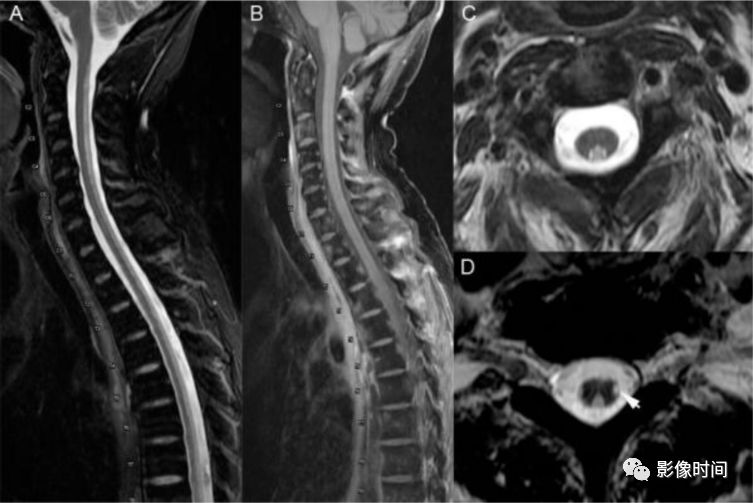

神经脊髓炎谱系疾病(neuromyelitis optica spectrum disorder,NMOSD):是一种由水通道蛋白-4(AQP-4)自身抗体介导的炎性脱髓鞘疾病,青年或中年女性较多见,临床常为双侧视神经炎和脊髓炎导致失明和截瘫,也可累及大脑。

MRI:

脊髓:病灶 T2WI 呈高信号,T1WI 呈稍低信号,急性期出现斑片状或云雾状强化,轴位常位于脊髓中央,长度>3 个椎体长度。亮点征:轴位 T2WI 很高信号的多发斑点,信号高于脑脊液,特异性=97%。

病灶分布于脊髓中央,长度大于3个椎体,亮点征